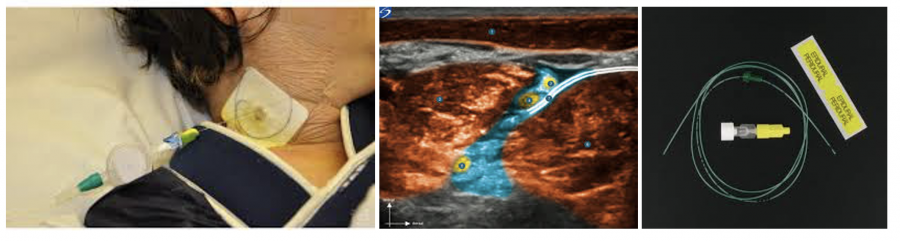

Blocs périnerveux continus

Objectif : placer un cathéter relié à une infusion continue (diffuseur élatomérique) sous contrôle échographique au contact d’un tronc nerveux ou d’un nerf pour obtenir une analgésie locorégionale (segment de membre )

Emplacements :

- Nerf fémoral : genou

- Nerf sciatique poplité : cheville et pied

- Plexus brachial : membre supérieur

- Espace parvertébral: paroi thoracique …

Prise en charge de la douleur sans morphinique

Faciliter la rééducation

Indications:

- Douleur post chirurgicale ou post traumatique- algodystrophie- Zona, syndrome de Parsonnage Turner- Douleur segmentaire du cancer- Poussée vaso occlusive drépanocytaire- ….